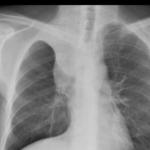

Sarcoid

Album: Sarcoid

Date: 04/20/2004

Size: 63 items

Views: 38651